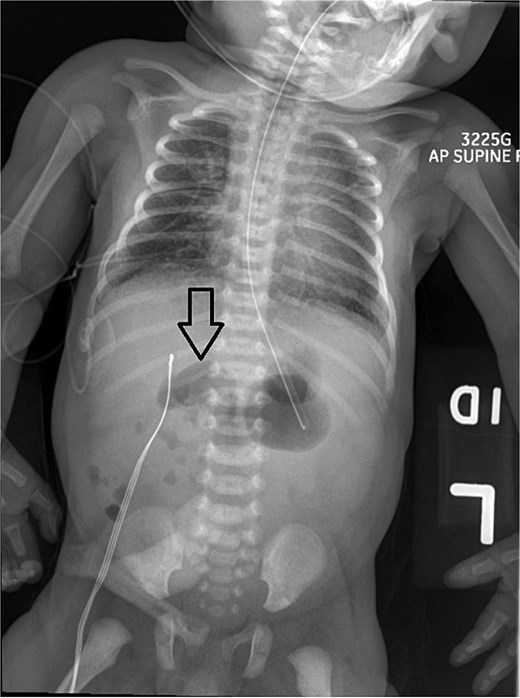

On Day 3 of life, she developed multiple episodes of bilious emesis and passed meconium-stained stools. An abdominal radiograph revealed gas-filled, non-distended bowel loops on the right and absence of small bowel gas on the left (Fig. 1), raising suspicion for malrotation. An upper GI (UGI) series confirmed abnormal duodenal positioning and obstruction, suggestive of malrotation with volvulus (Fig. 2). Emergent Ladd’s procedure was performed, revealing midgut volvulus with cloudy peritoneal fluid but viable bowel.

Abdominal X-ray shows nonspecific gas pattern with gas-filled, nondistended bowel loops on the right. Absence of small bowel gas on the left raises suspicion for malrotation.